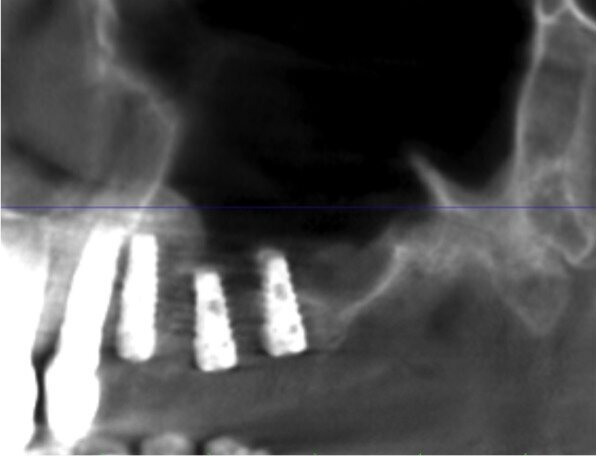

La paziente, di sesso femminile e con anamnesi medica negativa, si presenta in visita lamentando mobilità della protesi fissa presente nel II quadrante. Dopo l’esame obiettivo e strumentale gli elementi 23 e 27 (pilastri di ponte) vengono reputati non mantenibili e si programma l’estrazione degli stessi. Contestualmente all’estrazione si pianifica, con lo studio della CTCB pre-operatoria, l’inserimento di 3 impianti e la futura riabilitazione implanto-protesica fissa con pilastri di ponte 23-24-25. L’altezza di cresta residua è circa di 4/5 mm in altezza per le tre sedi (Figg. 1-4). La paziente riceve una profilassi antibiotica di tipo Short-term (Amoxicillina + Acido Clavulanico 2 g 1 ora prima dell’intervento) e fa uno sciacquo di 1 minuto con CHX 0,2% prima della chirurgia.

Fig. 1 - Sezione panorex CTCB pre-operatoria II quadrante con visione del seno mascellare.